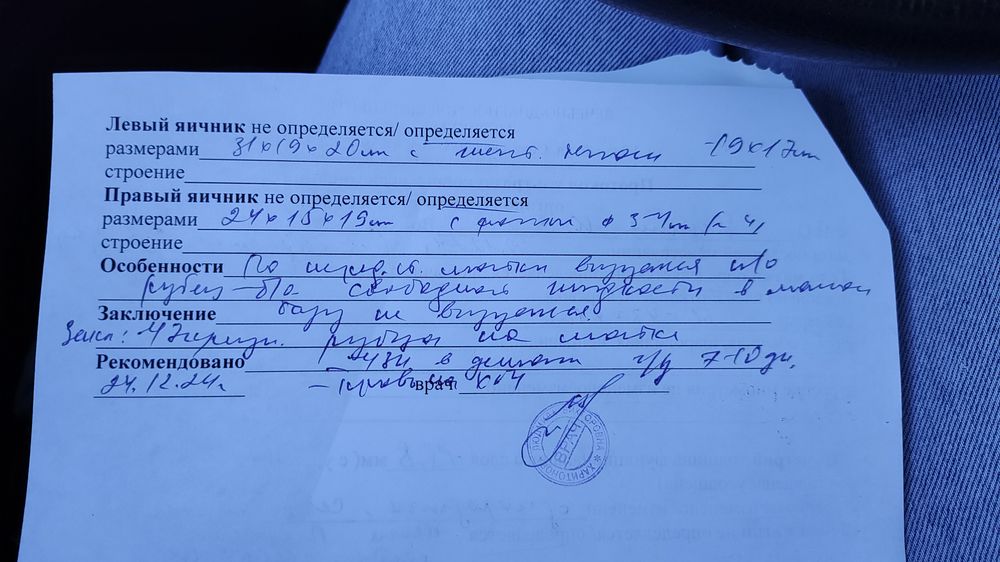

Сходила я сегодня на УЗИ. Лучше бы не ходила. В матке ничего нет. По последним М пять недель. Но факту гораздо меньше. Узистка говорит, что была поздняя овуляция. Числа 9 ПА был 7. Первая бледная полоска была 16 января. И скорее всего это был день прикрепления. Эндометрий хороший, ЖТ в левом яичнике. Я уже перепугалась за бхб. Купила эвик домой, а там почти сравнялись полосочки.